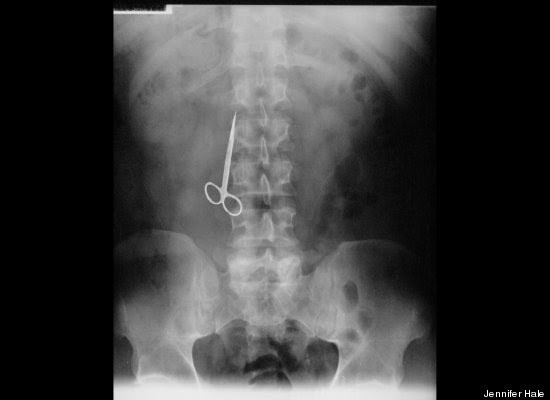

"Stack Up!" es una muy divertida colección de 100 imágenes de rayos X que muestra cuerpos extraños ingeridos o insertados en el cuerpo humano, tanto por accidente o de forma voluntaria, aunque se haga difícil imaginar el motivo de algunas de tales inserciones.

"Tenía las manos ocupadas", "me caí encima", son algunas de las excusas que los profesionales de la salud escuchan de los pacientes que llegan a los hospitales con "cuerpos extraños extrañamente metidos en el cuerpo".